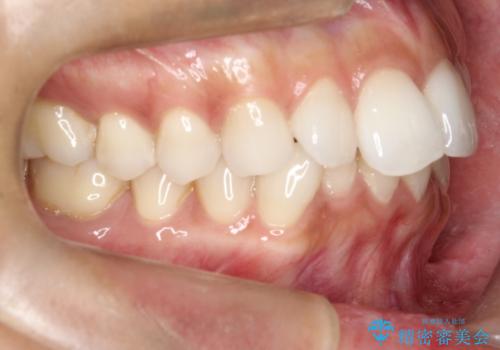

前歯のがたつきをマウスピース矯正で改善。IPRと遠心移動による非抜歯インビザライン治療

精密検査の結果、歯を並べるためのスペースが不足していましたが、抜歯をせずに改善したいというご希望があったため、IPR(歯の側面をわずかに削る処置)と、奥歯を後ろに動かす「遠心移動」を組み合わせる計画を立案。透明なマウスピース装置であるインビザラインを使用し、無理のない範囲でスペースを確保しながら歯列を整えることとしました。

治療では、マウスピースの設計に基づき、奥歯から順に後ろへ移動させる遠心移動を行い、前歯のためのスペースを作りました。同時に、数箇所の歯の間にIPRを施すことで、歯の健康に影響のない範囲で精密に隙間を確保しました。

1年半の治療期間を経て、重なり合っていた前歯はスムーズに整列し、理想的なアーチ状の歯並びへと改善されました。抜歯を行わずに治療を完了したことで、噛み合わせのバランスを維持しながら、審美性を大きく向上させることができました。現在は保定期間に入り、美しい状態を維持されています。